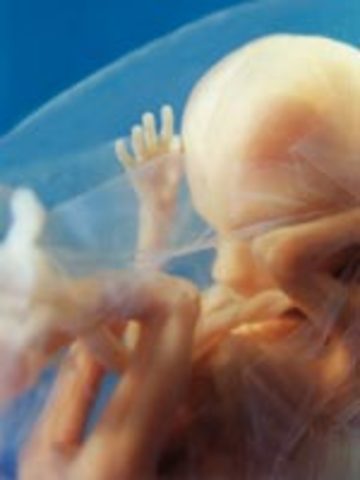

Fetus is 2.5 inches, starts moving spontaneously. Face begins to look like a baby face, pancreas produces insulin, the fingernails and toenails appear, baby can suck thumb and get hiccups baby can feel pain.

• Week 13

Week 13

Fetus is 3 inches, bones replace cartilage, external genitalia is almost defined.